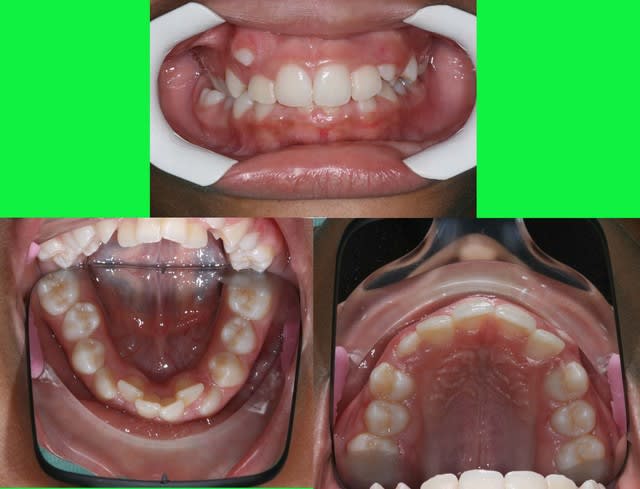

si ce n’était pas moi qui présentait ce cas (10 ans)

vous penseriez extractions ou pas d’extraction

P.S. : désolé, la photo en bas à droite est inversée

Photos du cas

voici les photos du m jour

bouche fermée

bouche ouverte

arcades

Photo en occlusion prise aujourd’hui